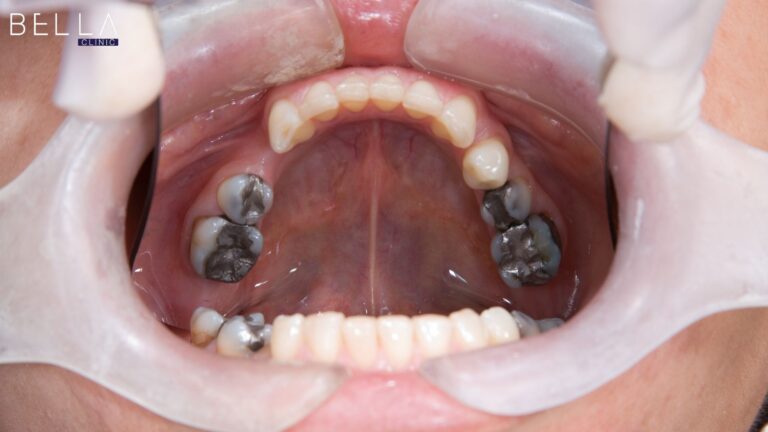

الابتسامة الصحية والكاملة هي مفتاح الثقة بالنفس وبوابة للتواصل الفعال. تأتي زراعة الأسنان في تركيا كحل ثوري ودائم لتعويض الأسنان المفقودة، حيث تعيد للابتسامة جمالها وللوجه تناسقه. هذا الإجراء هو عبارة عن غرس جذور اصطناعية من التيتانيوم في عظم الفك لتكون أساساً لأسنان بديلة ثابتة. وقد اكتسبت زراعة الأسنان شهرة عالمية بفضل فعاليتها ونتائجها التي […]